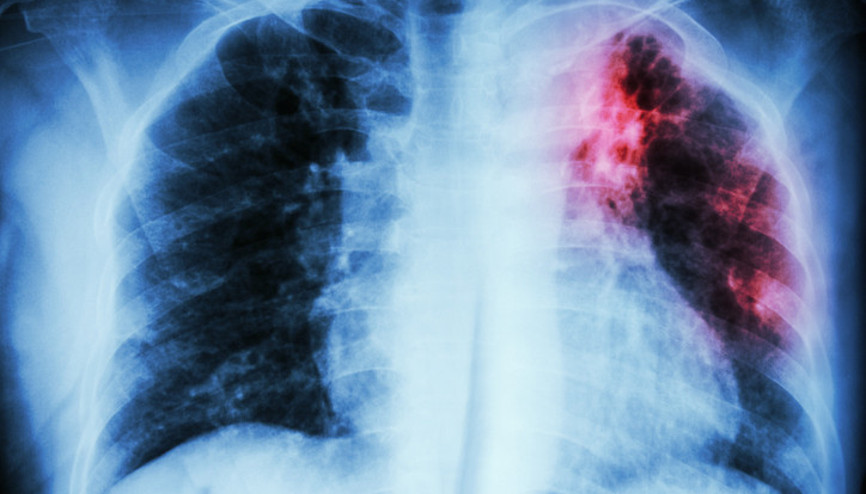

#SağlıkAkciğerlerin hava keseciklerinin en sık bakteriler, virüsler veya nadiren mantarlarla enfekte olarak iltihaplanması sonucunda zatürre oluşuyor. Dünyada her yıl yaklaşık 450 milyon kişiyi etkileyen bu hastalık, 4 milyona yakın insanın ölümüne neden oluyor. Grip veya COVID-19 gibi viral enfeksiyonlar da akciğerin savunma sistemini zayıflatarak bakteriyel zatürreye zemin hazırlıyor.

#SağlıkHalk arasında zatürre olarak bilinen pnömoni, akciğer dokusunun iltihaplanması sonucu oluşan bir hastalık. Dünyada ve ülkemizde hala en sık görülen enfeksiyonlardan biri olan zatürre aynı zamanda en önemli ölüm nedenleri arasında yer alıyor. Öyle ki ülkemizde her yıl yaklaşık 300 bin kişiye zatürre tanısı konuluyor. Sağlık Bakanlığı’nın 2023 yılı verilerine göre; hastaneye en çok yatış gerektiren bir enfeksiyon olan zatürre ölüm sebepleri arasında ilk 10'uncu sırada olmaya devam ediyor.

#ZatürreBursa’da, 5 yaşındaki Erdal Gazioğlu, gribal enfeksiyon sonrası gelişen zatürre nedeniyle yaşamını yitirdi. Bu acı olay, zatürrenin tehlikesini bir kez daha gündeme getirdi. Uzmanlar, üst solunum enfeksiyonlarının zatürre ile karıştırılmasının, hastalığın ciddiyetinin göz ardı edilmesine neden olduğunu vurguluyor. Prof. Dr. Muhammed Emin Akkoyunlu ise dünya genelinde her yıl yaklaşık 450 milyon kişinin zatürreye yakalandığını ve ülkemizde ise son bir aydır sayının arttığını belirtiyor. Peki zatürrede ölüme bile neden olan bu artışı nasıl yorumlamak gerekiyor? Belirtileri neler ve aşı ne kadar etkili?